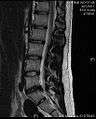

MRI scan of large herniation (on the right) of the disc between the L4-L5 vertebrae.

- Magnetic resonance imaging (MRI): A diagnostic test that produces three-dimensional images of body structures using powerful magnets and computer technology. It can show the spinal cord, nerve roots, and surrounding areas, as well as enlargement, degeneration, and tumors. It shows soft tissues even better than CAT scans. An MRI performed with a high magnetic field strength usually provides the most conclusive evidence for diagnosis of a disc herniation. T2-weighted images allow for clear visualization of protruded disc material in the spinal canal.